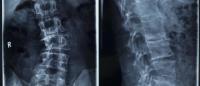

If there’s any asymmetry detected in your child’s shoulders, shoulder blades, spine, or pelvis, see a pediatric spine specialist to have an X-ray performed. If scoliosis is present, the doctor can measure the degree of curvature.

Vitale says treatment for children with a spinal curve of about 25 degrees can be treated without surgery by using scoliosis-specific physical therapy, vitamin D supplementation, and, sometimes, a brace.

There have never been better treatment options for children with scoliosis, Vitale adds. With more accurate body scans, X-rays that use barely any radiation, and more advanced bracing, the sooner treatment starts, the less likely it is that patients will need surgery, and the healthier they will be.

When the curve reaches 50 degrees, surgery is usually necessary.

Scoliosis that remains untreated can get worse. Once the curve hits the 70-degree stage, lung function may be impaired. Curves of 90 degrees or more can worsen both lung and heart function.